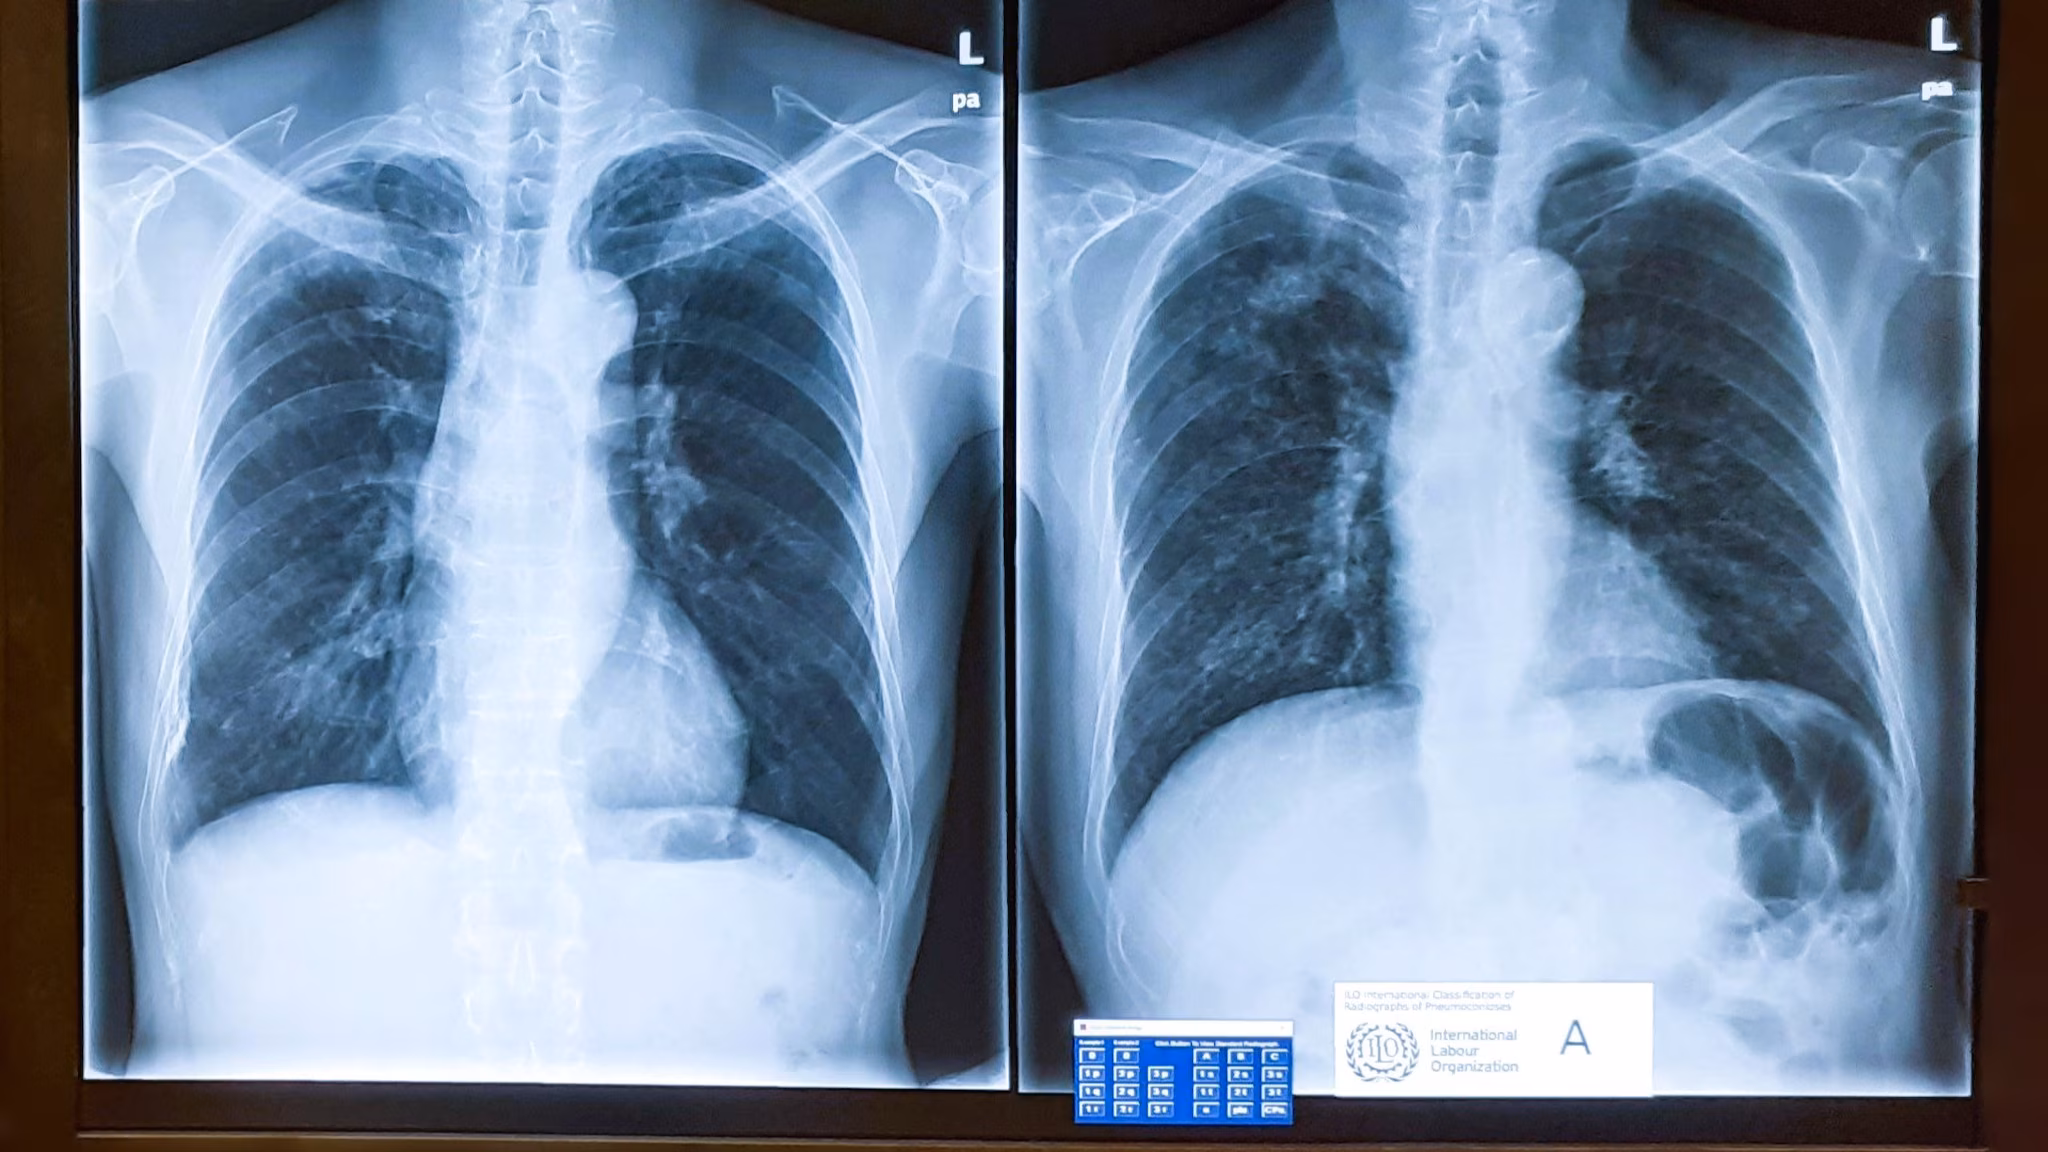

NIOSH strongly encourages adequate preparation prior to taking this exam. The NIOSH B Reader syllabus* is an important resource. The syllabus intends to familiarize you with the International Classification of Radiographs of Pneumoconioses. It also explains methods used to classify radiographs of dust-exposed workers. Most importantly, it provides examples showing the presence, shape, size, and profusion of opacities used in the ILO classification.